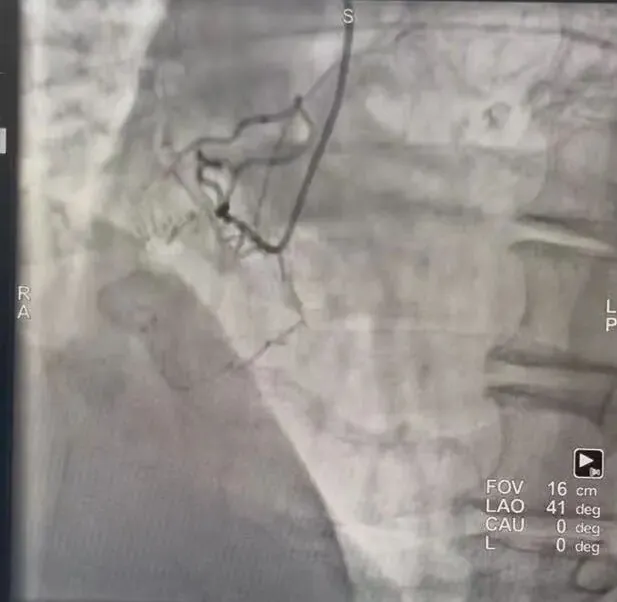

一周前,王大爷入院复查,经冠脉造影显示:之前回旋支植入支架良好,其右冠闭塞处没有残端,闭塞处又分支血管,闭塞段长且伴中重度钙化。通过双侧造影,发现前降支有两处侧枝循环逆向给右冠供血,但这种血管非常微小,逆向治疗难度大、风险高,可患者本人及家属仍有强烈手术意愿。

经南郑区人民医院心内二科介入团队充分评估及术前推演,制定了精准手术方案。9月23日上午,该科医疗团队密切配合,通过介入手术,在先处理好前降支血管后,借助这一微小的侧枝血管,将导丝及导管送到闭塞段远端,经多次尝试,运用最新的RPR策略,成功开通右冠。